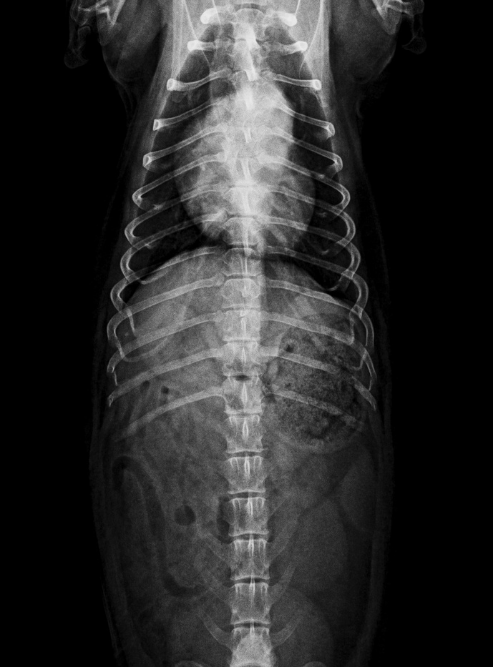

RX Severa Hemivertebra en T9 con desplazamiento del cuerpo vertebral hacia dorsal